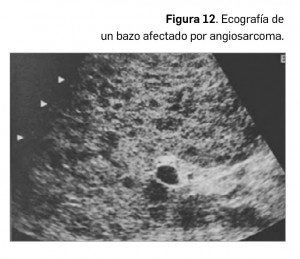

El diagnóstico diferencial de las lesiones esplénicas es amplio, dada la gran variedad de formas de afectación del bazo, siendo, la gran mayoría de las lesiones de apariencia inespecífica, difíciles de comprobar histológicamente. Por tanto, se hace necesario considerar el contexto clínico del paciente en el que se detecta una lesión o una anomalía esplénica.

Por otro lado, las lesiones focales esplénicas primarias son, en su gran mayoría, benignas, y salvo los quistes o hemangiomas, suelen presentar un comportamiento poco específico. Las más frecuentes presentan unas características de imagen que permiten realizar un diagnóstico de aproximación. Una lesión focal esplénica aislada en un paciente con cáncer, pero sin enfermedad metastásica diseminada, no suele corresponderse a una metástasis.